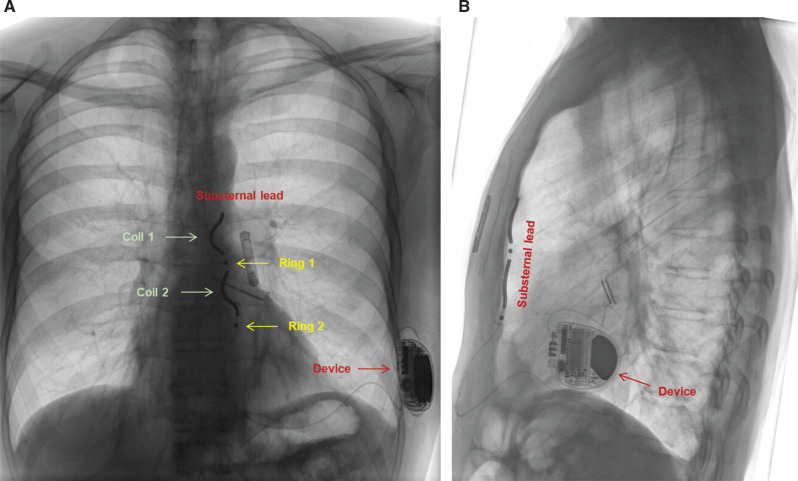

We present the case of a 52-year-old man suffering from malignant mitral valve prolapse syndrome. He underwent a right-sided thoracotomy for mitral valve repair but required implantable cardioverter-defibrillator (ICD) implantation 4 years later. He chose the option of a substernal ICD, which was implanted successfully without any complications and good electrical parameters.